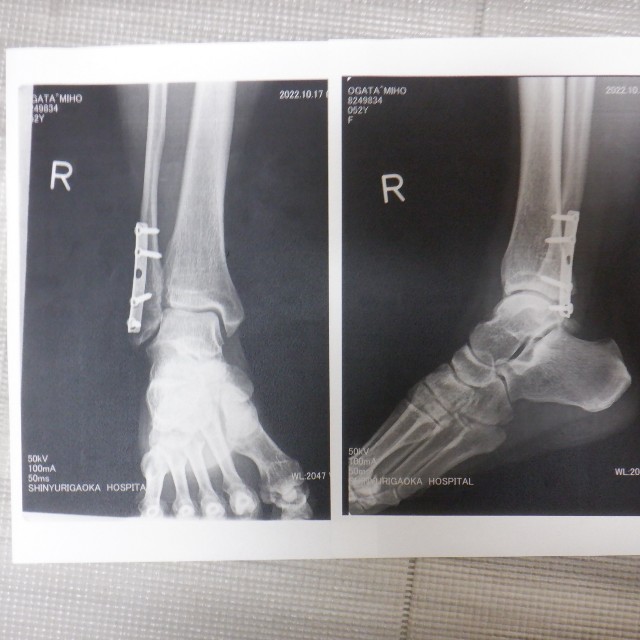

皆さんに大迷惑をおかけした「腓骨骨折」が10月7日。

あの時は自分の脛骨を目の当たりにし、「足首が崩壊した~」と目の前が真っ暗だったなぁ。

一年が経過し、診察も終了。

痛みや違和感はあるものの、先生からも「何をやっても良い」と言われました!(^^)!

振り返ってみると骨折してしまったのはダメダメだったけど、運ばれた病院も外傷再建センターという専門医がいる病院だったし、私自身健康で手術や傷の管理でトラブルもなかったし、ケガをしたところ以外はしっかり動かせる体力もあったし…。